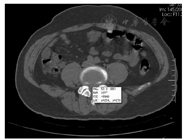

CT因具有良好的空间与组织密度分辨率,以方便检查、图像清晰、无侵人性伤害等优点广泛应用于LDH的诊断。其采用数字成像技术,因而能够分辨出肉眼不能分辨的组织结构间的轻微密度差别,并通过CT值来体现。广义来讲,CT值代表人体各种不同组织对X线吸收后的线性衰减系数。为了计算与论述的方便,Hounsfie将线性衰减系数化分为2 000个单位(称为CT值),并将水的CT值设定为零,做为相对值。人体各种不同组织结构的CT值界线有2 000个分度,最上界骨组织(骨密质)的CT值为1 000,最下界空气的CT值为-1 000。这种分度涵盖了人体各种不同组织结构,从密度最高的骨组织(骨密质)到密度最低的空腔器官内所含气体的(骨密质)值[5]。CT值会受多种因素的影响而发生改变,如管电压的高低、部分容积效应、周围间隙现象、光束硬化、视野的大小、扫描环内偏心和人体内存因素如呼吸、血流速度等,其中X线球管管电压的高或低影响最为重要。因不同管电压会产生不同强度的X线,即使在穿过光电吸收与反冲电子吸收比例相同的组织结构时其CT值也会出现偏差。由于这种偏差很小,对于临床诊断并无太大的影响,但在进行组织定量分析、比较同一组织结构内细微组织密度改变时,应当充分了解扫描时所采用的管电压的数值。否则,结果将会出现偏差,影响正确判断;其次,某一正常组织或病理组织的CT值还受部分容积效应和周围间隙现象的影响而出现CT值的偏差。在对椎间盘突出进行CT值测量时,扫描程序应选择重叠薄层扫描技术即层厚大于间距(层厚3 mm,间距2 mm),扫描架与所扫椎间隙一定要平行。如果扫描架与椎间隙不平行,或扫描层厚大于椎间盘厚度,则在同一扫描层面内至少含有两种以上不同组织密度又相互重叠的物质,即椎间盘与纤维软骨组织、疝出的髓核与椎管内结构,此时,则不能如实地反映该层面内各种组织本身的CT值。因此,扫描层厚与间距、扫描架与椎间隙之间的扫描角度将会直接影响椎间盘突出时其CT值测量数据的准确性,其中扫描厚度是导致CT值偏差的主要因素。在测量椎间盘突出的CT值时,小于扫描层厚的疝出部髓核虽然可以充分地显示,但所测得的疝出部髓核CT值并不具真实性。假如疝出部髓核组织密度比椎管内结构密度高,所测得的CT值则比实际要小;反之,所测CT值则比实际要高[6]。CT值等于该物质的衰减系数(μm)与水的吸收系数(μw)之差再与水的衰减系数相比之后乘以分度因素。物质的CT值反映物质的密度,即物质的CT值越高相当于物质密度越高。即CT值=α×(μm-μw)/μw。式中:α为分度因数,其取值为1 000时,CT值的单位为亨氏单位(Hu)。人体内不同的组织具有不同的衰减系数,因而其CT值也各不相同。按照CT值的高低分别为骨组织、软组织、脂肪、水、气体,水的CT值为0 Hu左右。依据定位的责任靶点,标记CT值可以很好反映腰椎间盘突出的病理类型、突出的精确位置及突出的严重程度,从而为LDH的诊断和手术治疗方法的选择及手术的实施提供重要的参考依据。LDH分区方法中标记CT值如图3所示。可对微创手术精准化手术方案予以完善。